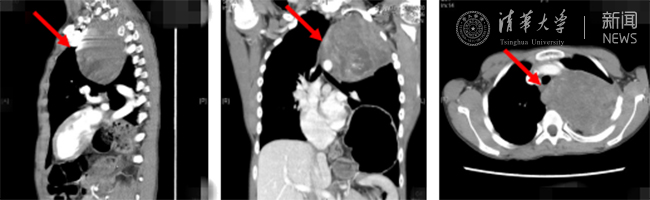

术后复查影像,患者体内的肿瘤已被切除。